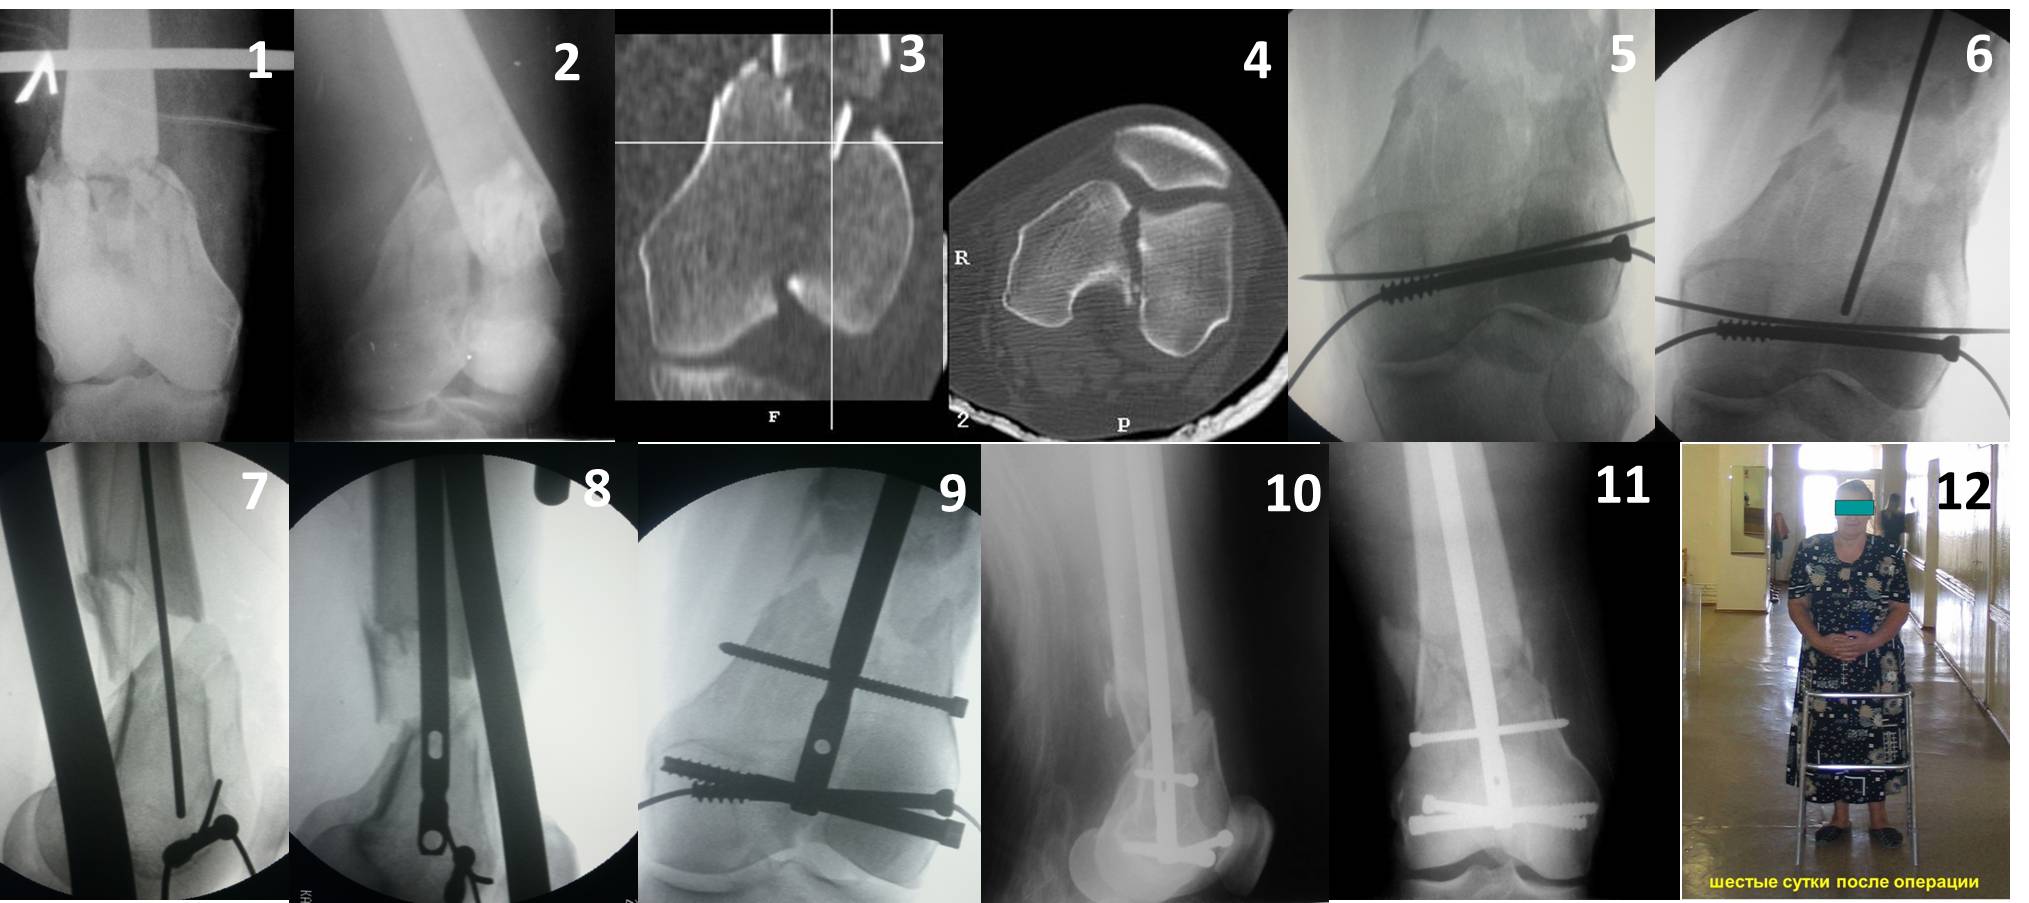

Ответ на эту часть Вашего поста – вложенный файл. Больная оперирована неделю назад по поводу открытого перелома дистального эпиметафиза бедренной кости. После операции она идёт в рентгенкабинет для выполнения послеоперационной контрольной рентгенографии, представленной на слайдах 10 и 11. Узнав, почему её фотографируют, просила передать Вам, Антон, привет.

В приложении пример недавней операции, C3, открытая репозиция, фиксация мыщелков спицами и винтами, ретроградный синтез большеберцовым гвоздем 10,5 мм диаметром, винты 5 мм.